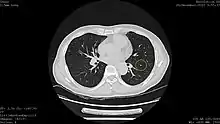

Results from large randomized studies have recently prompted a large number of professional organizations and governmental agencies in the U.S. to now recommend lung cancer screening in select populations. The 3 main types of lung cancer screening are low-dose, computerized tomographic (LDCT) screening, chest x-rays, and sputum cytology tests.[4] Currently multiple professional organizations, as well as the United States Preventive Services Task Force (USPSTF), the Centers for Medicare and Medicaid Services (CMS) and the European Commission's science advisors[5] concur and endorse low-dose, computerized tomographic screening for individuals at high-risk of lung cancer.

In the following years, the scientific community shifted its attention to computer tomography (CT). In 1996, results were published of a study of 1369 subjects screened in Japan that revealed that 73% of lung cancers that were missed by chest x-ray were able to be detected by CT scan.[19] Among the earliest United States-based clinical trials was the Early Lung Cancer Action Project (ELCAP), which published its results in 1999.[20] ELCAP screened 1000 volunteers with low-dose CT and chest x-ray. They were able to detect non-calcified nodules in 23% of patients by CT compared with 7% by chest x-ray. While this trial and a similar trial conducted by Mayo Clinic in 2005 demonstrated that CT was able to detect lung cancer at a higher rate than chest x-ray, both these trials used survival improvement, rather than mortality reduction, as an outcome, and thus were unable to prove that the use of CTs in lung cancer screening was actually impacting the number of people dying from lung cancer.[21][18]